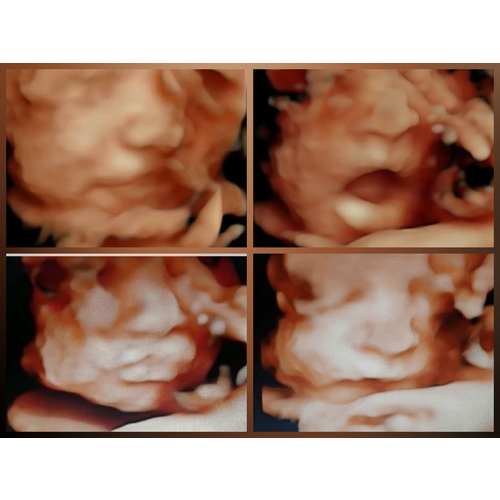

5 jaar geleden

Dit is ons boze meisje🤣 Ik blijf heel erg lachen om deze foto! Deze is met 27+4 gemaakt maar omdat mevrouw met haar voet op haar hoofd lag en weigerde te draaien mag ik maandag terug komen! Hopelijk ligt ze dan goed en is ze dan minder chagerijnig😂😂